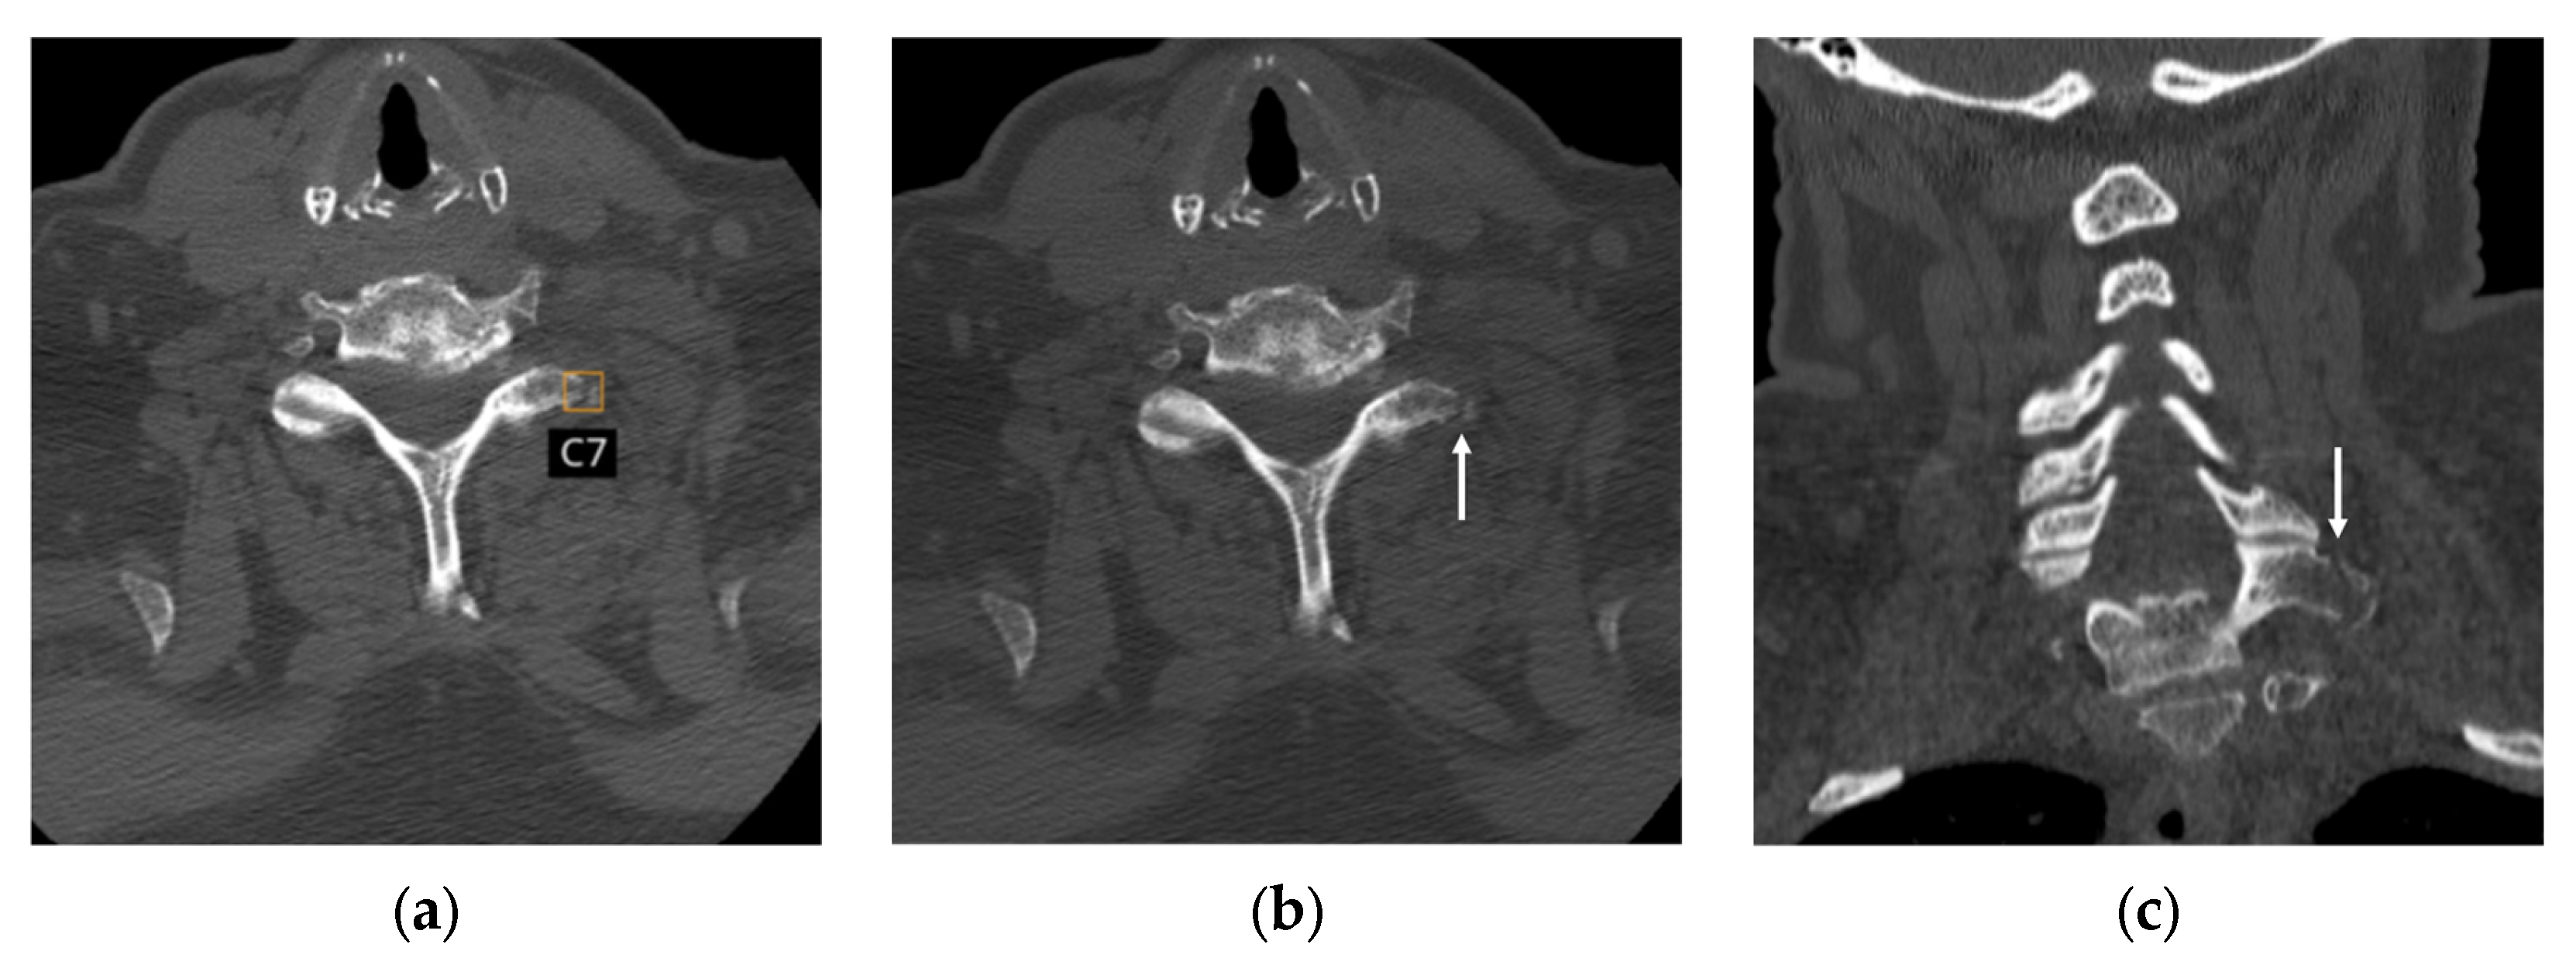

3.6. Analysis of False Positive and False Negative Cases